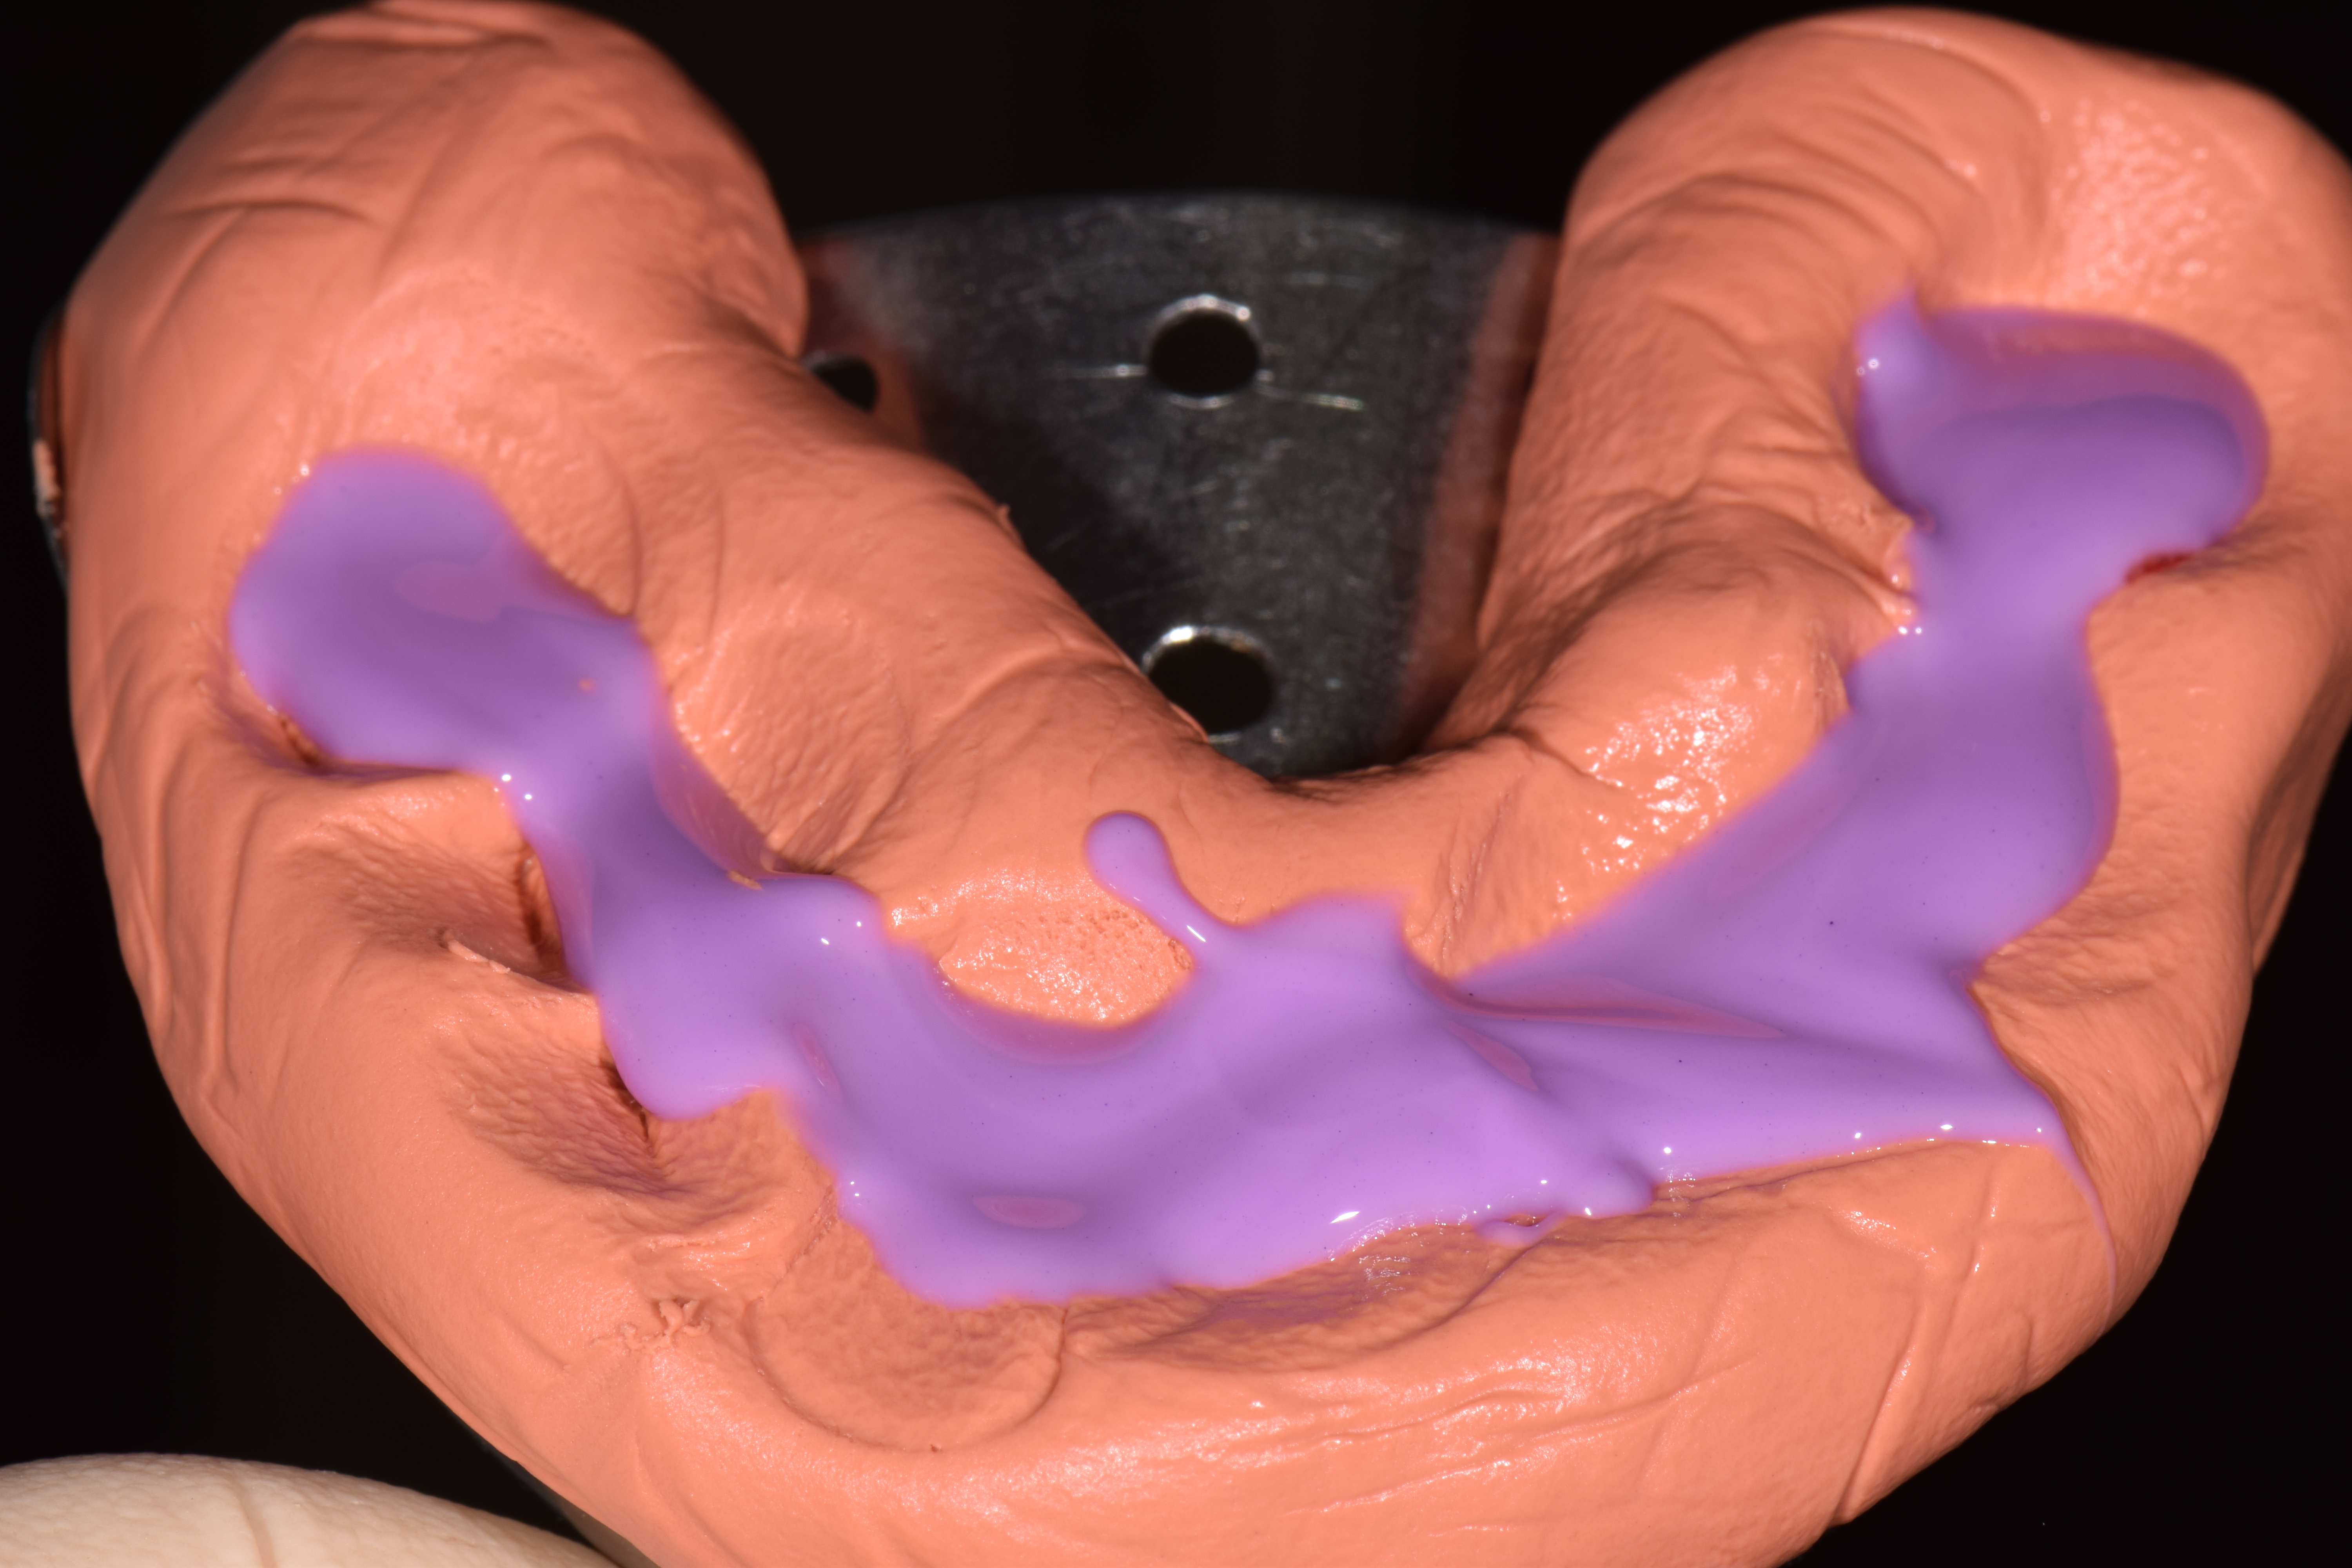

| ПРОТЕЗИРОВАНИЕ |

|

|

|

|

|

|